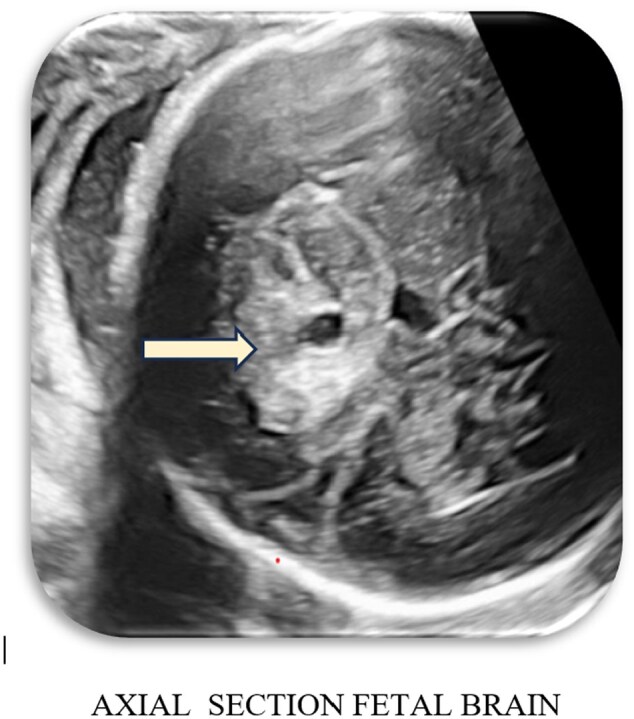

Unravelling fetal enigmas: a case of suprasellar lesion.